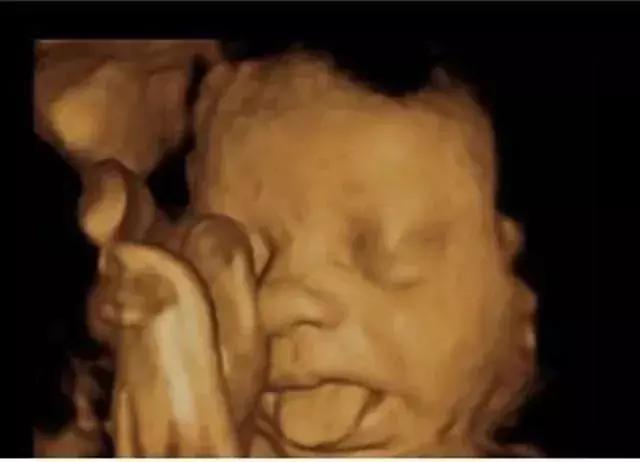

菌菌告诉你,小家伙不仅会做各种动作,表情更是丰富的不得了。

我还会吐舌头、扮鬼脸!